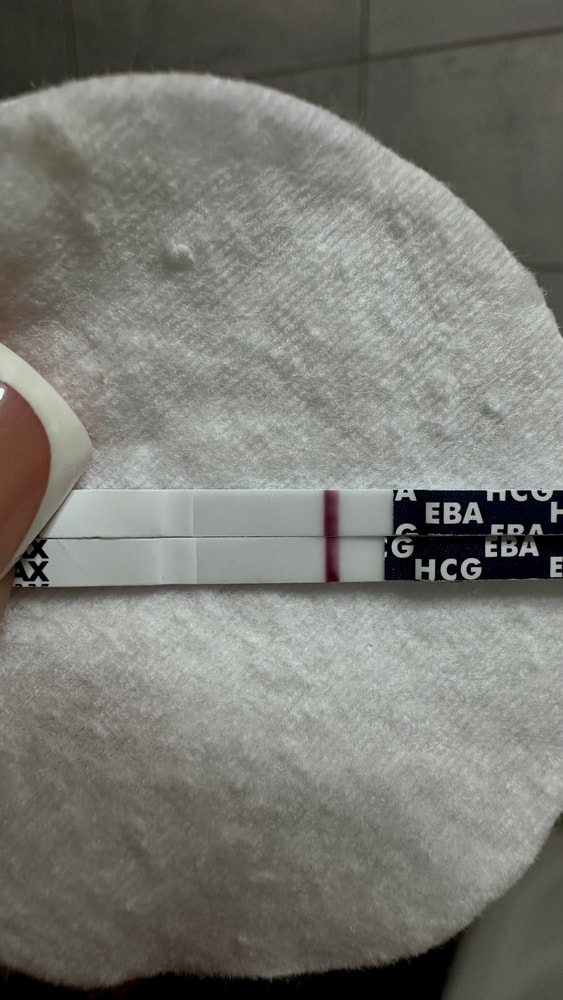

Может кто-то разбирается в узи? Не знаю какая это киста.